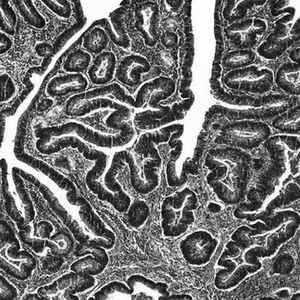

结直肠癌是几种对男性影响比女性严重的癌症之一。

6月21日发表于《自然》杂志的两项研究均涉及对男性侵袭性特别强的癌症:结直肠癌和膀胱癌。其中一项研究发现,随着男性年龄增长,某些细胞中的Y染色体会自然丢失,从而增加患侵袭性膀胱癌的风险,并可能使膀胱肿瘤逃避免疫系统的检测;另一项研究则发现,老鼠体内一种特定的Y染色体基因会增加结直肠癌扩散到身体其他部位的风险。

在另一项研究中,一个研究小鼠结直肠癌的团队发现,Y染色体上一个名为KDM5D的基因可能会削弱肿瘤细胞之间的联系,从而帮助这些细胞分裂并扩散至身体其他部位。当该基因被删除时,肿瘤细胞的侵袭性减弱,更容易被免疫细胞识别。论文作者之一、美国得克萨斯大学安德森癌症中心研究人员Ronald DePinho说,这为抗癌治疗提供了一个潜在靶点。“这是一个可用药物治疗的目标。”